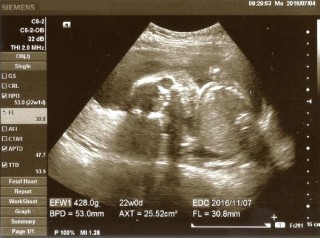

写真:22w2d:すもも♪さん

お医者さんから「性別って知りたい?」と聞かれましたが、既に私の目でも分かりました。お股に何もついてなーい!女の子の可能性が高いとのことです♪(*^▽^) 頭の大きさ:53.0mm、体重:428.0g 元気に育って大きくな~れ。 ※エコー写真は足ではなく顔です。